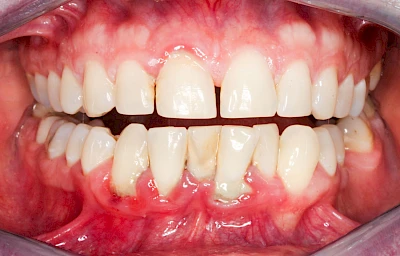

Bakterien in den Zahnbelägen greifen neben den Zähnen auch das Zahnfleisch (Gingiva) und den gesamten Zahnhalteapparat (Parodont) an. Der Körper reagiert mit einer Entzündung, sichtbar als Rötung und Schwellung. Meist blutet das Zahnfleisch z .B. beim Essen oder auch beim Putzen der Zähne.

Ist zunächst nur das Zahnfleisch von der Entzündung betroffen, spricht man von Gingivitis. Später, wenn auch der Knochen um die Zähne herum entzündet ist, spricht man von einer Parodontitis. Bei der Parodontitis wird der Knochen nach und nach abgebaut und das Zahnfleisch zieht sich zurück. Die Zahnhälse und Zahnwurzeloberflächen liegen mehr und mehr frei. Die Zähne werden zunehmend lockerer und fallen schließlich aus.